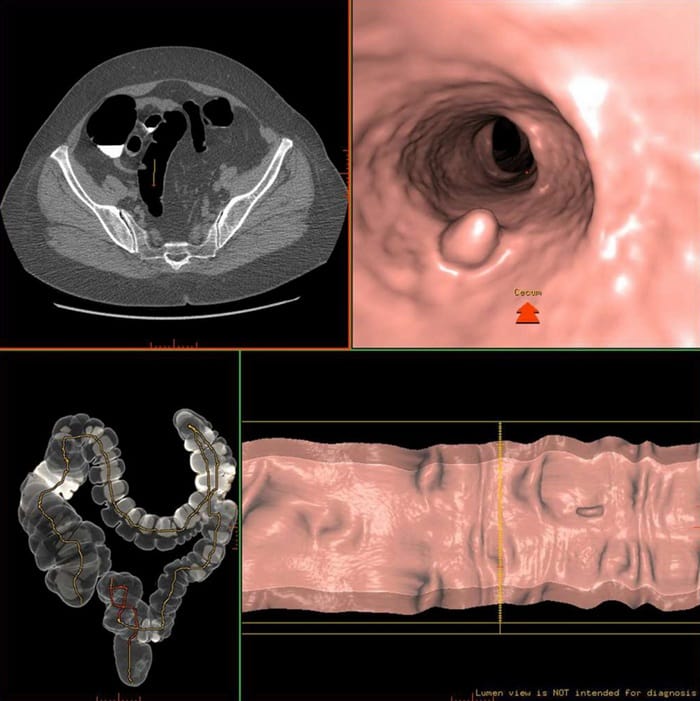

2.1. Chụp CT Scanner đại tràng (nội soi ảo)

Chụp CT Scanner đại tràng, còn gọi là nội soi ảo đại tràng, là kỹ thuật chẩn đoán hình ảnh hiện đại sử dụng máy CT cắt lớp đa dãy để tái tạo hình ảnh 3D toàn bộ đại tràng mà không cần đưa ống soi vào cơ thể. Trước khi chụp, người bệnh có thể được bơm khí hoặc thuốc cản quang vào ruột để hình ảnh rõ nét hơn. Phương pháp này giúp phát hiện polyp ≥6 mm, khối u, hẹp ruột hoặc bất thường niêm mạc một cách nhanh chóng và chính xác.

Ưu điểm:

- Không xâm lấn, không đau, phù hợp cho người sợ nội soi truyền thống.

- Thời gian thực hiện nhanh, chỉ khoảng 10–15 phút.

- Cho hình ảnh 3D rõ nét, dễ quan sát toàn bộ đại tràng.

Nhược điểm:

- Không phát hiện được polyp nhỏ <5 mm.

- Không thể sinh thiết hoặc cắt polyp khi phát hiện tổn thương.

- Có sử dụng tia X (bức xạ ion hóa) nên cần cân nhắc ở người chụp nhiều lần.

- Độ chính xác trung bình 85–90%, thích hợp cho sàng lọc ban đầu hoặc theo dõi sau điều trị.

Chụp CT để khám đại tràng nhanh chóng, không xâm lấn